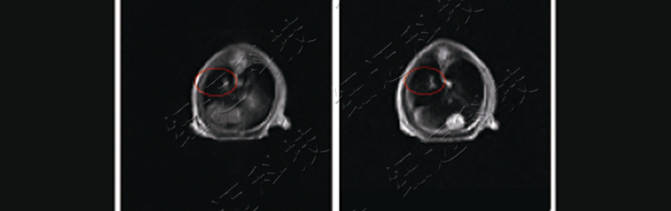

4、裸鼠肺部原位肿瘤位置排查